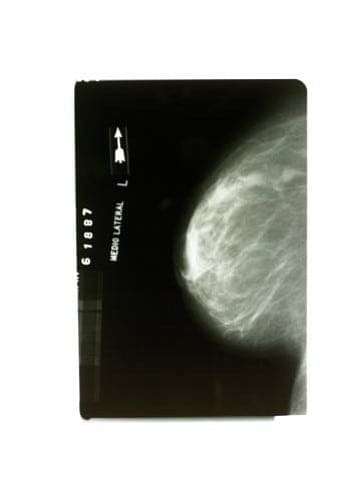

Mammogram. A mammogram is an X-ray of the breast. Mammograms are the best method to detect breast cancer early when it is easier to treat and before it is big enough to feel or cause symptoms. Having regular mammograms can lower the risk of dying from breast cancer. If you are age 40 years or older, be sure to have a screening mammogram every one to two years.